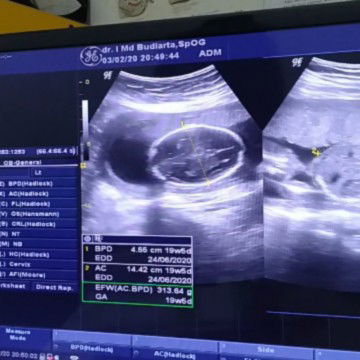

Cara membaca hasil USG untuk mengetahui berat bayi dalam gram dapat melihat istilah Estimated Fetal Weight (EFW)